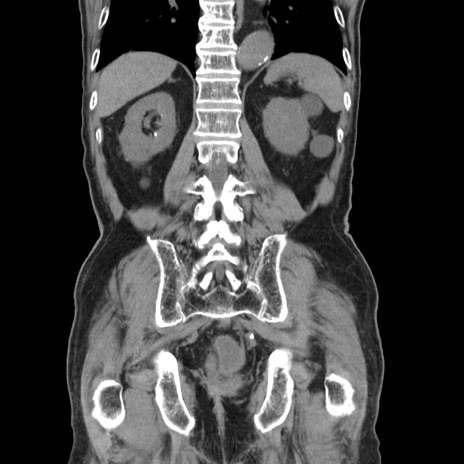

矢状断像

【症例】80歳代男性

【主訴】左側腹部痛、嘔吐

【現病歴】本日早朝より左腹部に痛みあり。昼頃嘔吐認めたため、救急要請。

【既往歴】直腸癌(Mile手術)、胆摘

【身体所見】意識清明、BT 35.9℃、BP 221/93mmHg、SpO2 97%(RA) 、腹部:左ストーマ周囲に限局性の腹部膨隆あり。 膨隆部自発痛・圧痛あり・軟。

【データ】WBC 7700、CRP 0.09